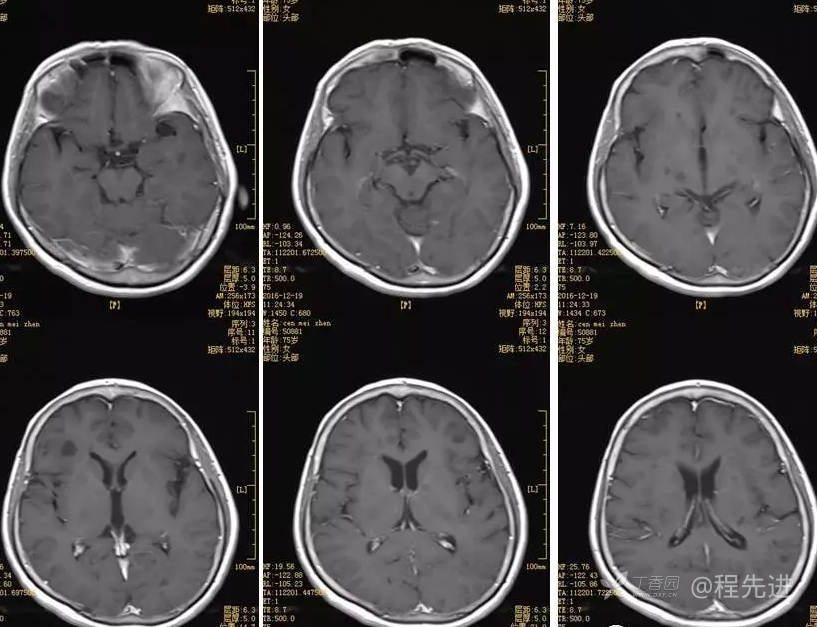

3月特别精彩病例|头晕伴左侧肢体乏力、行走不稳1周【结果已公布】

患者性别:女

患者年龄:75岁

简要病史:头晕伴左侧肢体乏力、行走不稳1周。否认高血压、脑梗塞、肝炎、糖尿病、肺结核病史。否认疫区疫水接触史。

体格检查:神经系统查体正常